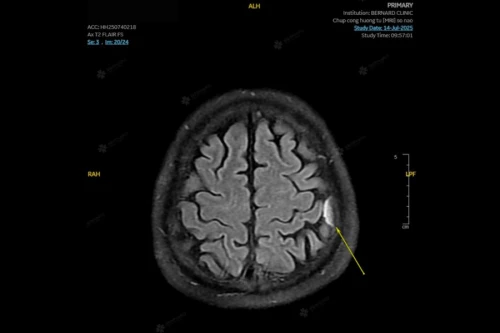

Hai tổn thương bất thường ở não và mạch máu não

Kết quả MRI của nữ bệnh nhân bất ngờ ghi nhận đồng thời hai tổn thương nghiêm trọng, tiềm ẩn nguy cơ lớn đến tính mạng nếu không được phát hiện và xử trí kịp thời.

- U màng não (có vôi hóa) ở vùng trán phải, nằm sát bản sọ.

Đây là loại u não phổ biến nhất ở người lớn, phần lớn lành tính. Tuy nhiên nếu không được chẩn đoán sớm, u có thể gây tăng áp lực nội sọ, tổn thương thần kinh vĩnh viễn, xuất huyết trong u, thậm chí tử vong nếu u phát triển nhanh hoặc ở vị trí nguy hiểm.